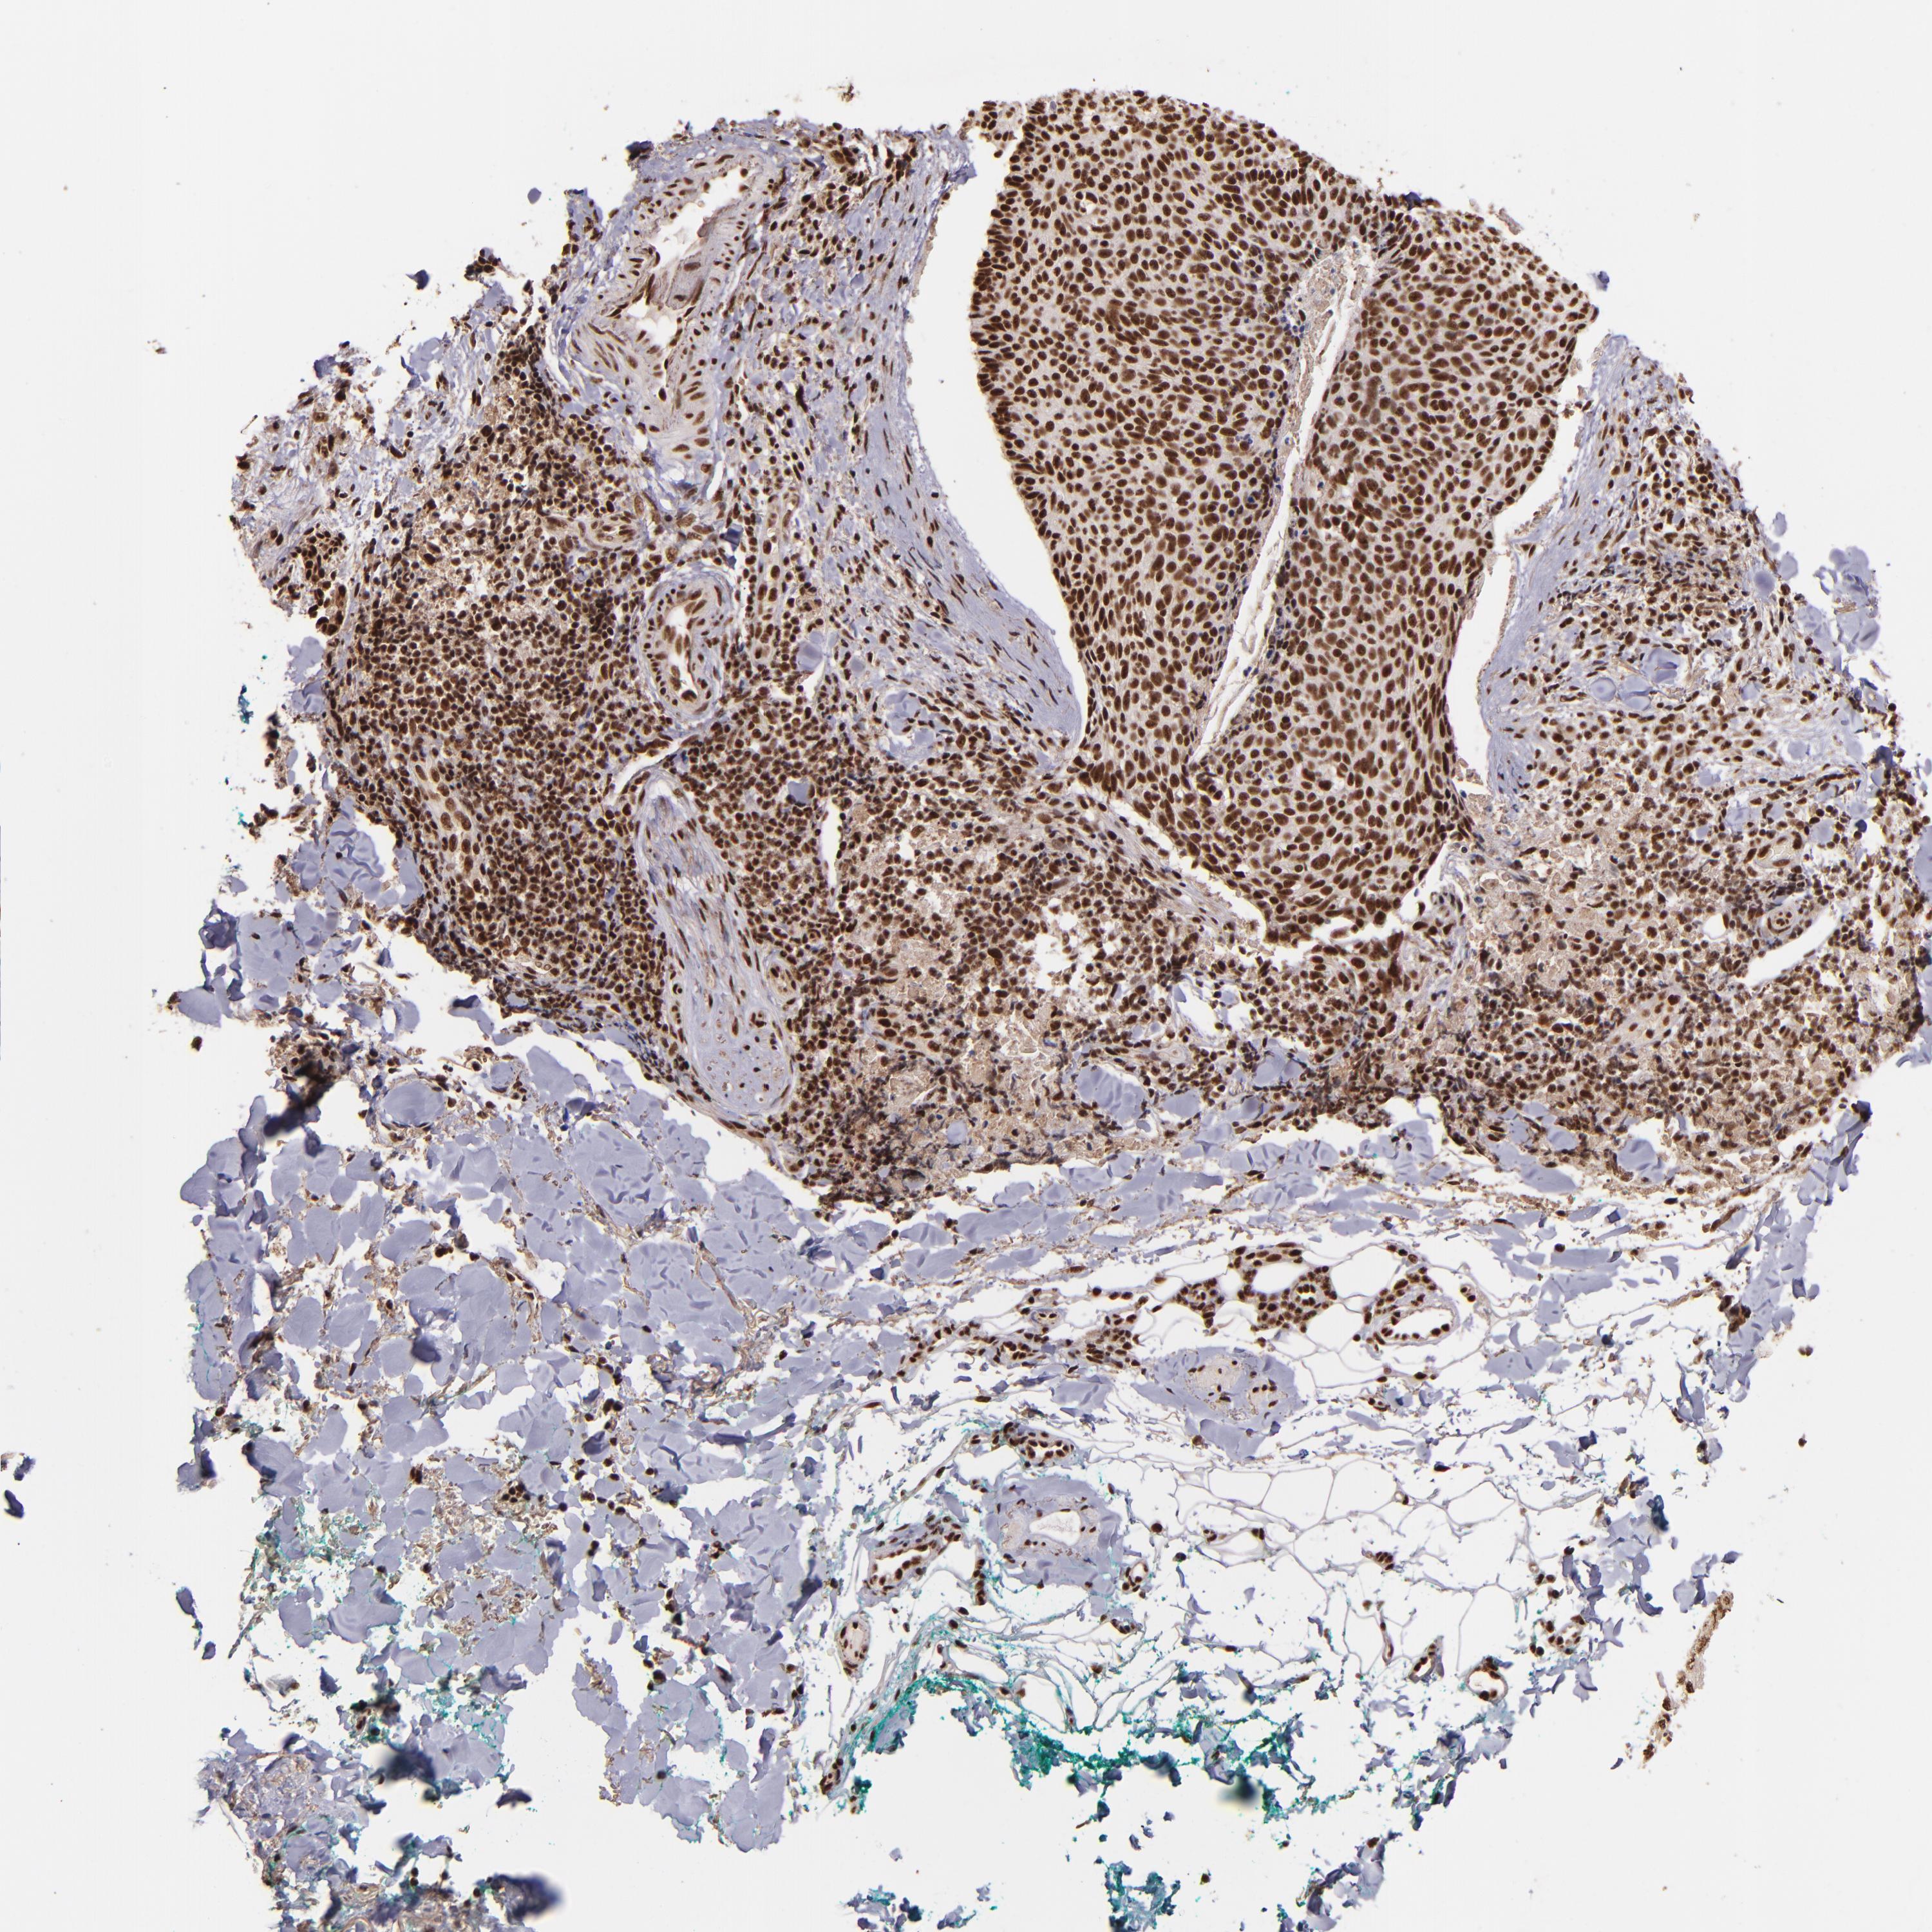

Basal cell and squamous cell cancer

SKIN CANCER - Protein expressioni

A mouse-over function shows sample information and annotation data. Click on an image to view it in a full screen mode. Samples can be filtered based on level of antibody staining by selecting one or several of the following categories: high, medium, low and not detected. The assay and annotation is described here.

Antibody stainingi

Antibody staining in the annotated cell types in the current human tissue is reported as not detected, low, medium, or high, based on conventional immunohistochemistry profiling in selected tissues. This score is based on the combination of the staining intensity and fraction of stained cells.

Each image is clickable and will lead to virtual microscopy that enables deeper exploration of all samples and also displays staining intensity scores, fraction scores and subcellular localization as well as patient and tissue information for each sample.

Antibody HPA001880

Staining

High

Intensity

Strong

Quantity

>75%

Location

Nuclear

Squamous cell carcinoma, NOS

Basal cell carcinoma